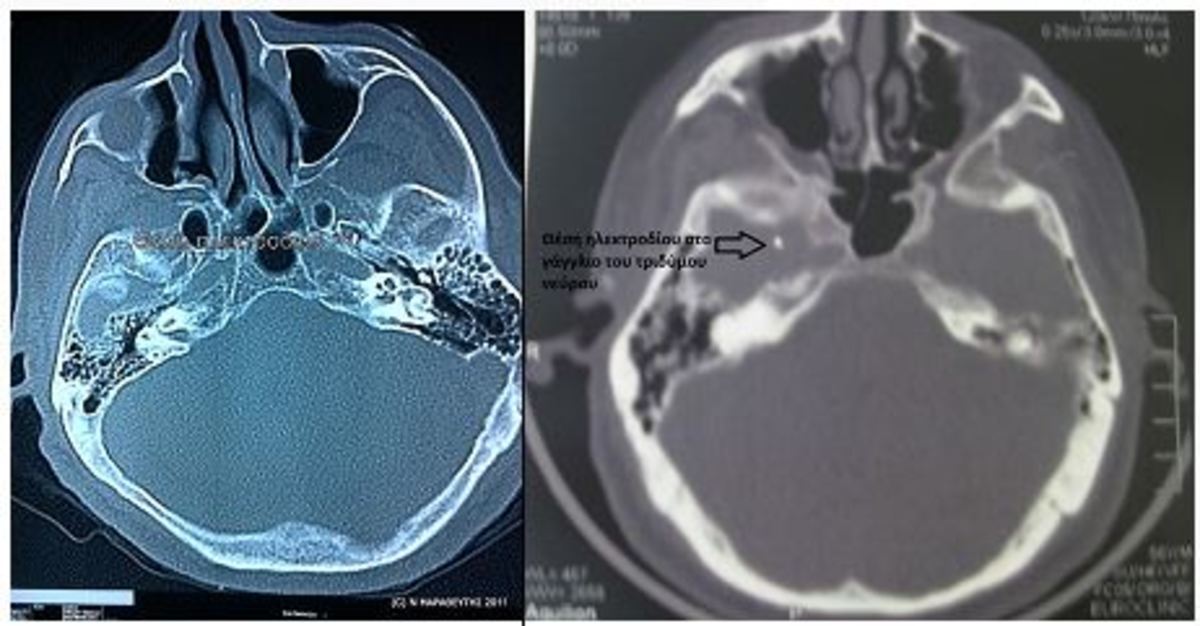

Eίναι η πλέον σύγχρονη, ελάχιστα επεμβατική και ασφαλέστερη μέθοδος αντιμετώπισης της νευραλγίας. Η χρήση του αξονικού τομογράφου κάνει 100% ακριβή την προσπέλαση του στόχου, ελαχιστοποιώντας την πιθανότητα τραυματισμού του εγκεφάλου, του νεύρου, ή ενός σημαντικού αιμοφόρου αγγείου. Έτσι, η επέμβαση γίνεται με ασφάλεια και αποτελεσματικότητα.

Έχοντας ιδανική στόχευση, εισάγουμε ένα ειδικό ηλεκτρόδιο σε μορφή βελόνας, μέσα στο ωοειδές τρήμα που βρίσκεται στη βάση του κρανίου και αποτελεί το σημείο εξόδου του τριδύμου νεύρου, όπως αυτό διακλαδώνεται για να νευρώσει το πρόσωπο. Παράλληλα, για να ελαχιστοποιηθεί η πιθανότητα πρόκλησης επώδυνης αναισθησίας του νεύρου, γίνεται ταυτόχρονα και ηλεκτροφυσιολογικός έλεγχος και δοκιμαστική θερμοπηξία, για άμεση εκτίμηση και ακριβέστερη εντόπιση του θεραπευτικού αποτελέσματος, το οποίο αντιλαμβάνεται άμεσα ο ασθενής.